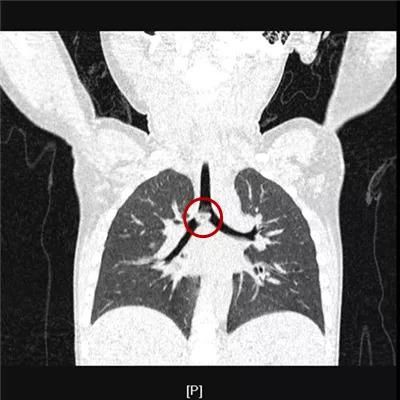

5小时余前食用瓜子后有可疑呛瓜子,后出现咳嗽伴气喘。位于气管分叉处,您还能看出瓜子君的本来面目吗?

文章图片